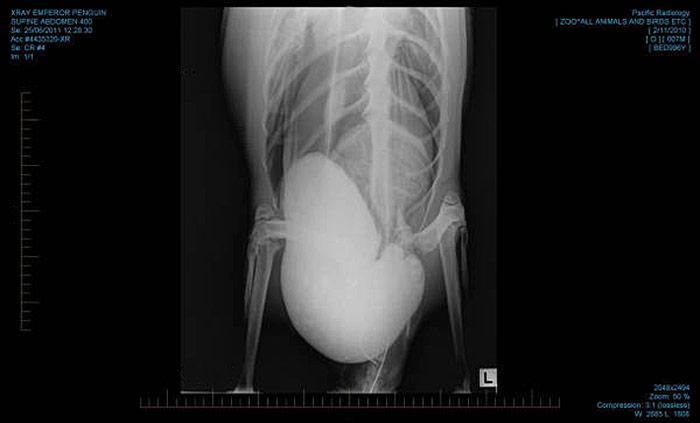

Das Klima in Neuseeland war für den jungen Kaiserpinguin offenbar zu warm. Um der Überhitzung entgegenzuwirken futterte «Luckyfeet» den weissen Sand der Kapiti-Küste, im Irrglauben es handle sich um Schnee. Wenn es Pinguinen zu Hause in der Antarktis zu warm wird, fressen sie Schnee, um sich abzukühlen. Der Zustand des Kaiserpinguins war bei der Einlieferung ernst, aber stabil. Die Überlebungschance bestand etwa bei 50%. Der Kaiserpinguin wurde ins künstliche Koma versetzt und insgesamt vier Mal operiert. Das 27 Kilogramm schwere Tier hatte die Eingriffe gut überstanden und knabberte danach in einem klimatisierten Raum an Eisstückchen.